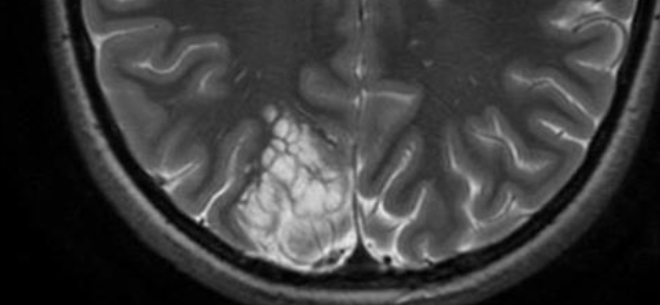

- Apparence en “Bulles de Savon” sur le T2 (supprimée en FLAIR)